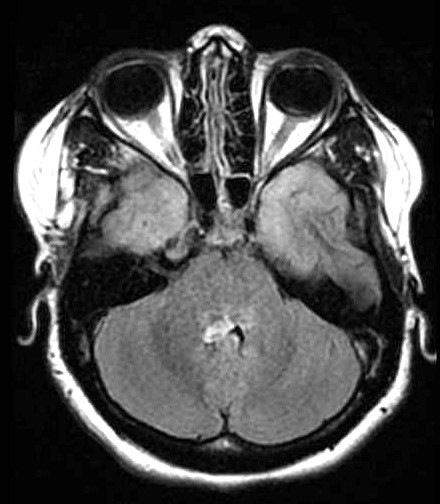

| Fem. 17a. |

| Nódulo sólido homogêneo preenchendo o III ventrículo, com limites precisos, com hipossinal em T1 e hipersinal em T2 e FLAIR, que se impregna por contraste paramagnético. Lesão menor implantada no assoalho do IV ventrículo provavelmente representa disseminação por via liquórica. |

| F. 17a. Tumor teratóide rabdóide atípico de III ventrículo. RM | HE | VIM, GFAP | HHF35, desmina, 1A4 | AE1AE3, EMA |